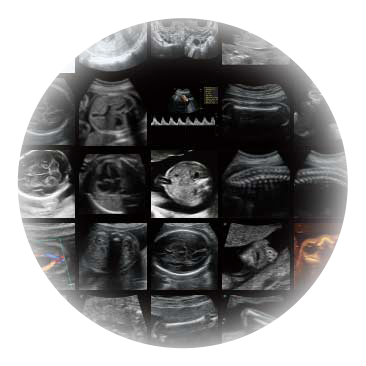

作为P系列家族成员之一,P40 Plus采用DB中国旗舰官方网站高端超声系统平台——极光,并以时尚秀丽、小巧灵动的外观设计绽放出灵动之韵、科技之美。高端平台的使用保证了P40 Plus优质的基础图像;完备的高级功能可满足您全身应用的基本需求;丰富的探头配置、多样的高级4D成像及分析软件为您日益增多的妇产应用需求提供丰富的诊疗方案。

宽频带腹部凸阵探头和腹部容积探头、大角度腔内探头和腔内容积探头、独特的生殖专用曲柄探头,为妇产应用提供全面诊疗方案。

卵泡结构的自动识别和测量,可显示多组测量数据。